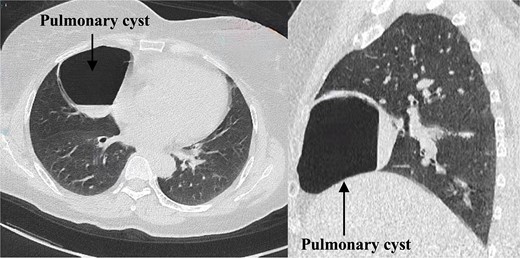

The patient was admitted on 20 March 2024. Enhanced chest CT revealed a solitary cystic lung lesion in the right middle lobe, measuring 8.0 cm × 7.3 cm, with a thin wall and slight compression of the right cardiac border (Fig. 1).